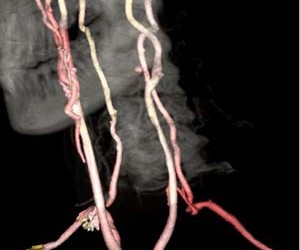

Furtul subclavicular-vertebral (vertebral-subclavian steal syndrome) apare în condițiile unei stenoze (de obicei prin placă de aterom, dar și în cadrul arteritei cu celule gigante sau arteritei Takayasu) a arterei subclavii înainte de emergența arterei vertebrale. În aceste condiții, încărcarea cu sânge a arterii subclaviculare distal de stenoză se face prin furt din artera vertebrală, ceea ce duce la scăderea fluxului sangvin către teritoriul cerebral posterior (irigat de sistemul vertebro-bazilar). Ca mecanism compensator, fluxul în artera vertebrală de partea opusă este crescut, pentru a asigura atât fluxul normal din artera bazilară cât și fluxul retrograd de furt din artera vertebrală afectată. În repaus fenomenul este silențios din punct de vedere clinic, dar în condiții de mobilizare a brațului artera subclavie fură mai mult sânge din artera vertebrală și pot apărea manifestări ischemice cerebrale (insuficiență vertebro-bazilară: amețeală, cefalee, AIT). Adesea furtul nu este suficient pentru nevoile brațului, ceea se se traduce prin dureri ischemice (claudicație) și puls slab. Diagnosticul se face prin ecografie Doppler, arteriografie sau angioCT. Tratamentul este chirurgical (excizia plăcii de aterom sau bypass) sau intervențional (angioplastie percutană cu stent). O situație și mai complicată este cea în care există fenomen de furt subclavicular-vertebral pe o parte iar artera vertebrală de partea opusă este stenozată/hipoplazică, ceea ce înseamnă că încărcarea subclaviei în porțiunea distală nu mai poate veni decât din sistemul carotidian, prin comunicantele posterioare și apoi prin bazilară.

Referințe: Subclavian Steal Syndrome, foto: radiologymri.blogspot.com